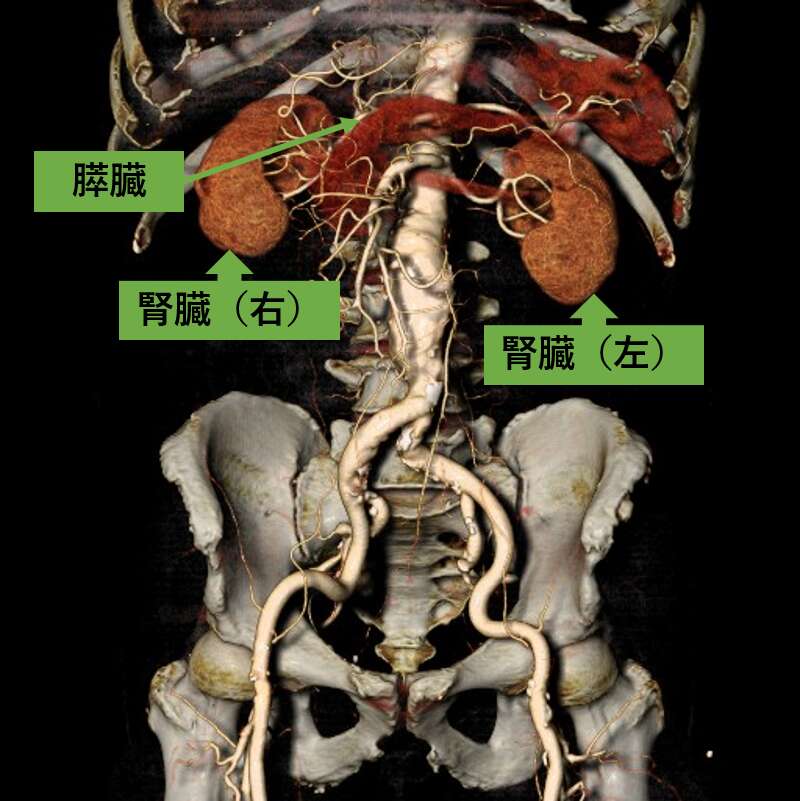

造影剤を用いて撮影すると、臓器や血管の3次元画像を作成することができます。3次元画像では、あらゆる角度から立体的に観察することができ、診断・治療に用いられています。

腹部血管 3次元画像

図中の赤丸は腹部の大動脈が「瘤状」になっていることが分かります。

3次元画像にすることで動脈瘤の大きさ、形状、他の臓器や血管との位置関係が把握しやすくなります。